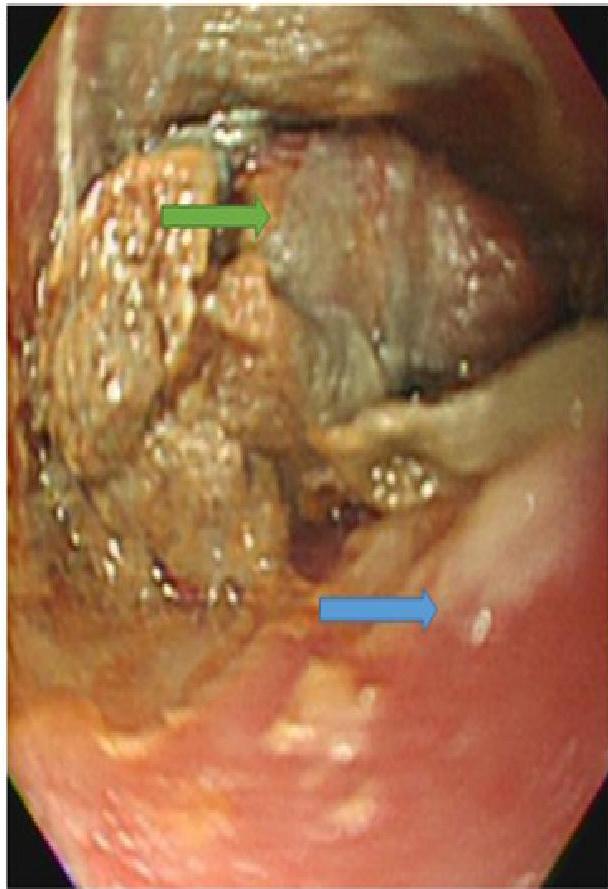

The “Button Battery” Emergency Risk

- Risks: Esophageal burns, fistula formation (tracheoesophageal), hemorrhage.

- X-Ray Sign: “Double Halo” or “Step-off” sign on lateral view.

- Action: Immediate removal required if stuck in the esophagus.

A, B, C: Imaging examples of button battery ingestion.